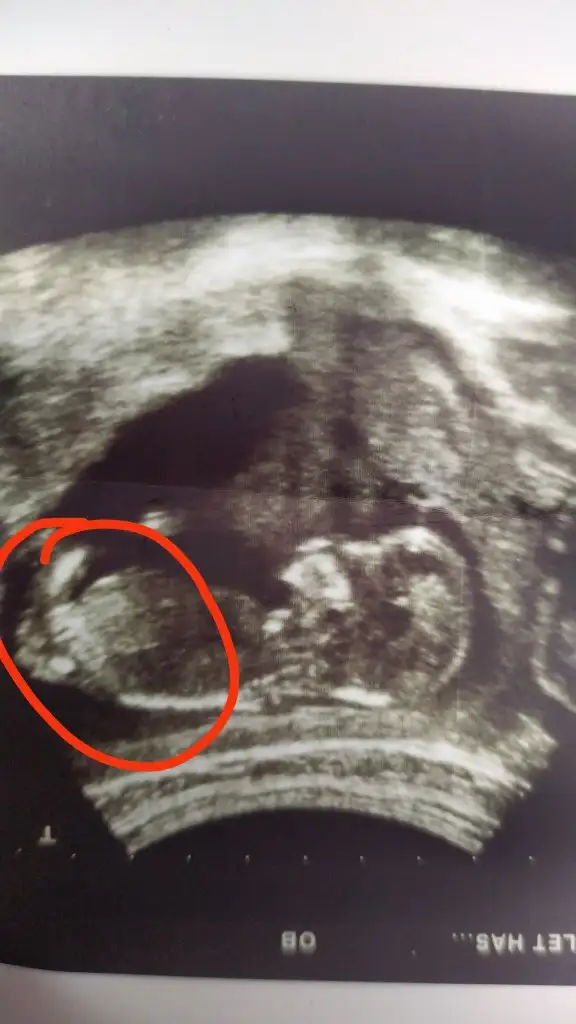

Ama anlamadığım genital bölgede üç çizgisi var dikkatli bakınca anlaşılıyor doktor baktı pipisini göremiyorum dedi iki hafta sonra net olur dedi belki küçüktür pipisi dedi anlamadım bende pipi yok diyip sonradan oluşabilir demesi felan

Birincisi senin işaretli olan yerde genital bölgede üç çizgi var dikkatli bakınca anlaşılıyor ikincide benim ki ay inşallah kızdır iki kızım olmasını çok istiyorum iki oğlum var zaten tek fark senin ki 11 haftalıkken benimki 13+5 Ken olan resimleri